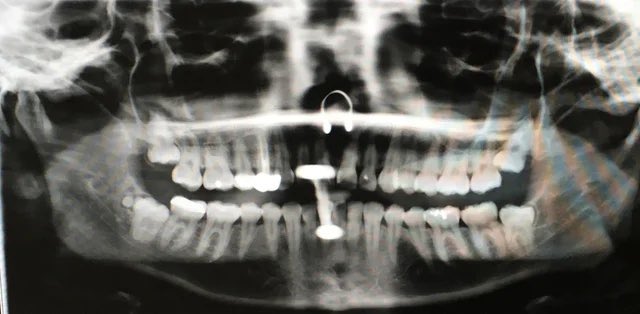

مع انتشار استعمال الحلق في منطقة الشفة واللسان.. أجد من واجبي التحذير من مضارها على المدى البعيد كإنحسار اللثة1️⃣أو تفرق الأسنان4️⃣والمدى القريب كالإلتهابات الحادة2️⃣وكسور الأسنان 3️⃣

فوجود هذه الاجسام المؤذية في مناطق دقيقة وحساسة غير مستحب

-افساد اشعة الرئس والعنق